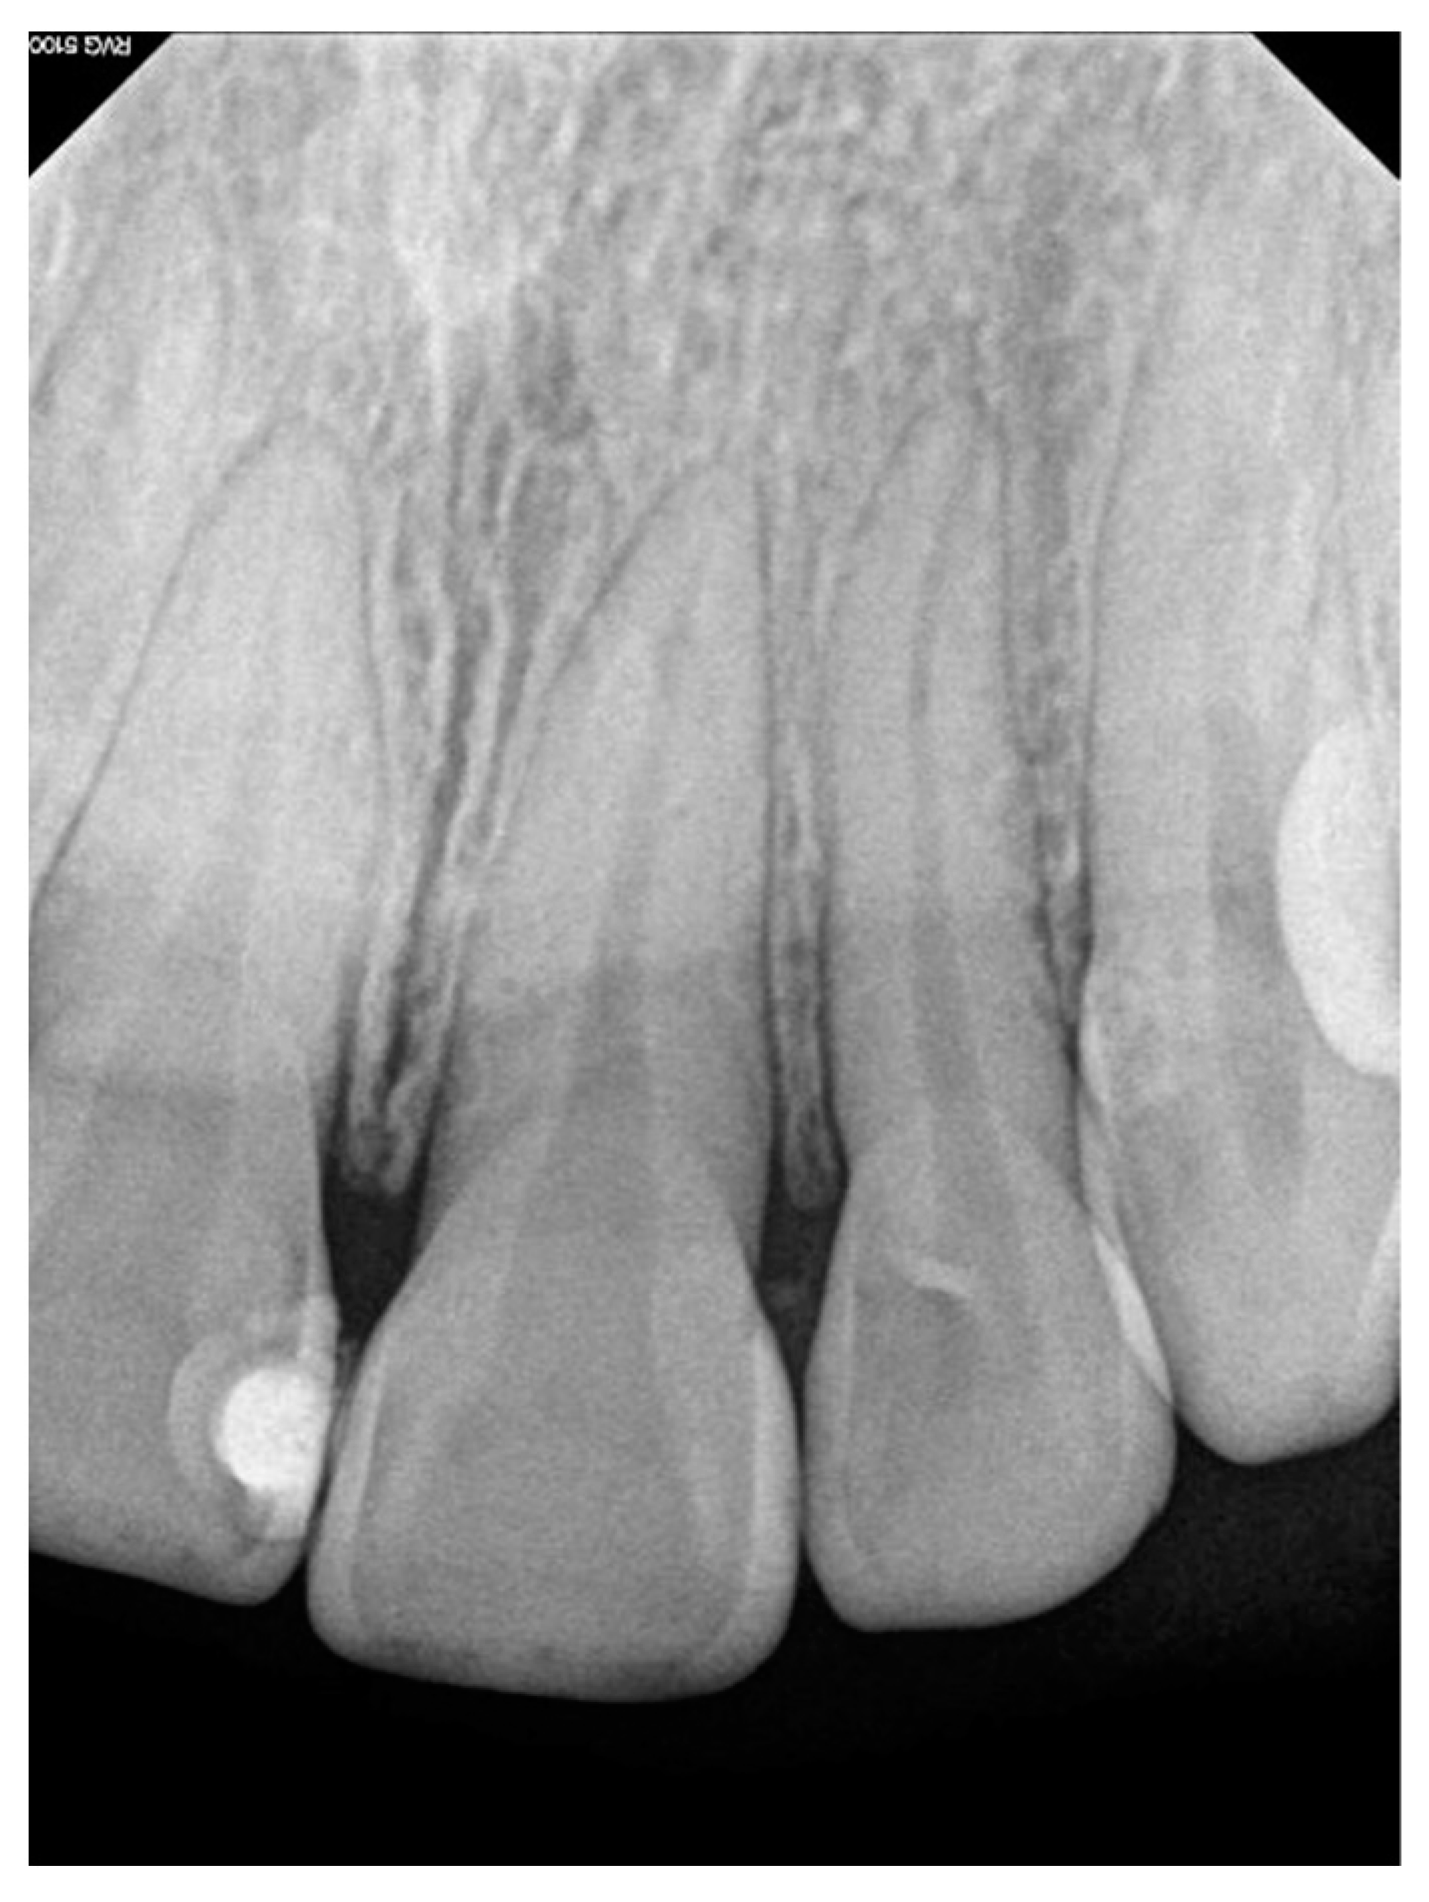

Intraoral clinical examination identified an increase in the volume of the gum (measuring 1.0 cm × 0.7 cm × 0.3 cm) located between the central and upper left lateral incisors, and partially filling the vestibular space. On palpation, the area presented a soft consistency, a rough texture, an oval base with slight mobility, and a pink coloration with irregular margins but without bleeding or pain (Figure 1). Furthermore, a probing depth of 9 mm was recorded vestibularly. Subgingival calculus and plaque were present. Contradictorily, there were no signs of dental mobility and the patient referred no symptomatology. Intra-oral peri-apical radiograph revealed no pathological findings or any signs of bone loss, root resorption, or increased periodontal ligament space (Figure 2). A complete blood count was performed and all blood results were within normal limits. Based on the information obtained from the historical, clinical, and radiographic examinations, a presumptive diagnosis of pyogenic granuloma or PGCG was considered.

Figure 2. Periapical radiograph of the affected dental organs without the presence of bone disease.